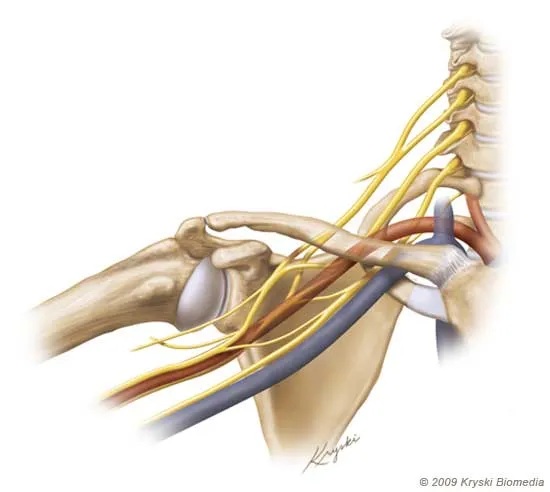

Compression, tension, and resultant damage of the nerves of the brachial plexus cause the symptoms of neurogenic TOS. However, the brachial plexus is quite complex, comprising different nerve fibers, with multiple branches and divisions. Compression of different fibers or branches will cause different symptoms. Additionally, compression may only occur in certain positions of the arms and neck. As a result, patients may fail to understand why they are experiencing pain at certain times, in certain occupations or recreations. Nonetheless, patients suffer considerable pain of different types and causes.

As we know, the subclavian artery, subclavian vein, and brachial plexus pass through each thoracic outlet in close proximity. Furthermore, the mechanisms of compression are relatively similar for all types of thoracic outlet syndrome. Thus, a patient with thoracic outlet syndrome can experience compression of 1, 2, or all 3 of these vital structures. In fact, many patients with neurogenic thoracic outlet syndrome have significant compression of the subclavian vein, but without a blood clot. Since this compression impairs venous drainage of the arm, swelling or edema of the arm can result. As a result, symptoms of neurogenic thoracic outlet syndrome may be magnified. In that case, treatment to relieve the venous compression helps relieve neurogenic thoracic outlet syndrome.

Imaging of patients with neurogenic TOS provides valuable information to the TOS specialist. While a TOS specialist may strongly suspect that his or her patient has neurogenic TOS, the clinical examination has poor sensitivity and accuracy. Therefore, several outstanding questions must be answered. Firstly, can compression or tension of the brachial plexus be proven? Second, is there intrinsic disease of the brachial plexus? Third, can alternative diagnoses, such as a herniated disc, be ruled out? Fourth, what are the exact anatomic structures that cause compression or tension of the brachial plexus? Fifth, does arm motion contribute to compression? Finally, what other structures are involved, such as arteries or veins?

MRI can show the soft tissues of each thoracic outlet in great detail. Scalene muscles and their anomalies, fibrous bands, the brachial plexus and its branches, and the fat that surrounds these structures are very well seen. Bones such as the clavicle, scapula, first rib, cervical rib, and cervical spine can also be seen. MRI can be performed with the arms in different positions. Radiologists can see the changes that arm motion causes.